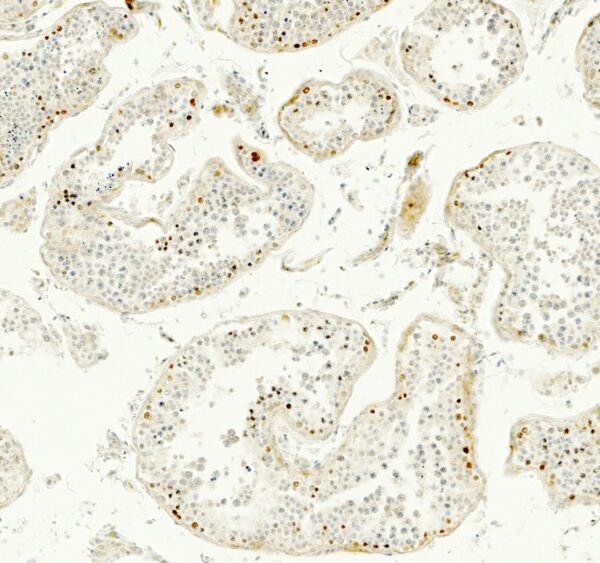

- Immunohistochemistry (IHC)

- Chromogenic IHC, single marker per slide